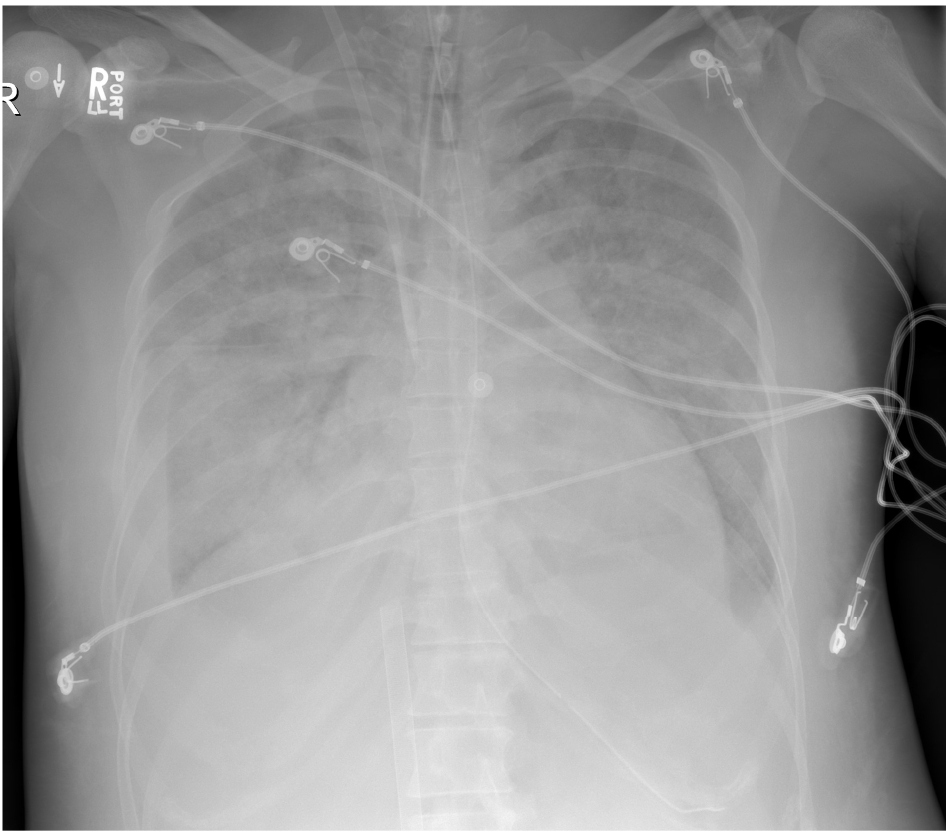

A diagnosis of thyroid storm was made, the Intensive Care Unit (ICU) was consulted and while in the ED, she was treated with intravenous (IV) doses of furosemide and metoprolol, and placed on bilevel positive airway pressure (BiPAP) ventilation. Her arterial blood gas was 7.17/18/300/6 while on 100% FiO2 with a lactate level of 10.8 (normal 0.5-1.6 mmol/L). Shortly upon arriving to the ICU, and about 6 hours after presenting to the ED, she had a witnessed pulseless electrical activity (PEA) arrest. She received 5 rounds of CPR, a total of 3 mg epinephrine and was intubated. The hospital’s ECPR team was activated. There was return of spontaneous circulation (ROSC) at 10 minutes. She then re-arrested within minutes of her initial ROSC and was placed on a LUCASÓ device for mechanical CPR. By 29 minutes into her second arrest, she was successfully cannulated and received ECPR via VA-ECMO. The patient was in dense cardiogenic shock on milrinone, epinephrine, norepinephrine and vasopressin infusions. A post-cannulation bedside transesophageal echocardiogram (TEE) was performed and revealed severe biventricular failure with a left ventricle ejection fraction (LVEF) of approximately 5%. She was cooled to a temperature of 35-36 degrees Celsius for 24 hours. Anti-thyroid medications consisting of thioamides, potassium iodide (Lugol’s) solution and corticosteroids were initiated. Due to her metabolic acidosis and anuric renal failure, she was placed onto continuous renal replacement therapy (CRRT). Her chest X-ray following intubation, cannulation and ROSC is shown in Figure 2. She was negative for SARS-CoV 2 virus on both nasopharyngeal swab and tracheal aspirate.

Figure 2: Chest X-Ray post arrest.